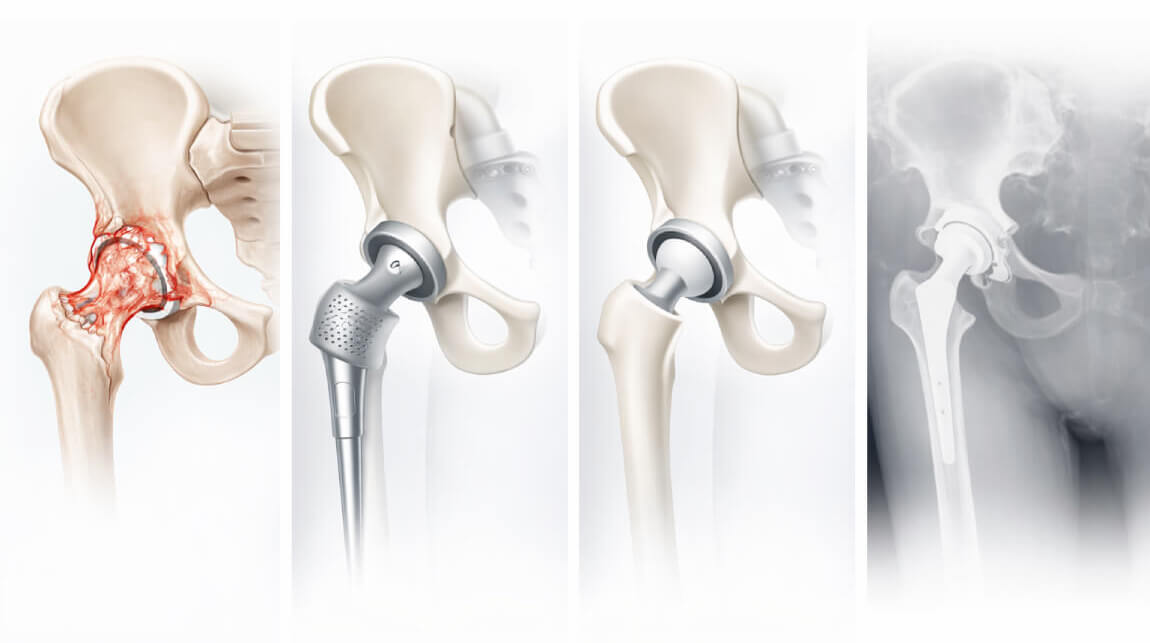

Endoprotezoplastyka (zastąpienie stawu sztucznym stawem) to bardzo skomplikowany i ryzykowny zabieg, który często prowadzi do różnych powikłań, w tym utraty samodzielności i niepełnosprawności.

Jeśli nie zostaną podjęte odpowiednie działania na czas, dochodzi do całkowitej utraty stawu. A jedynym rozwiązaniem jest operacja, podczas której staw zostaje zastąpiony sztucznym. Jednak nalegam, aby nie dopuszczać do takiego etapu. Sam zabieg wymiany stawu często kończy się infekcją, która może prowadzić nawet do amputacji dotkniętej części ciała!

Zdjęcie z operacji, podczas której staw został zastąpiony sztucznym stawem.

W 60–70% przypadków dochodzi do odrzucenia endoprotezy, co skutkuje nieznośnym, przewlekłym bólem oraz całkowitą utratą funkcji kończyny.